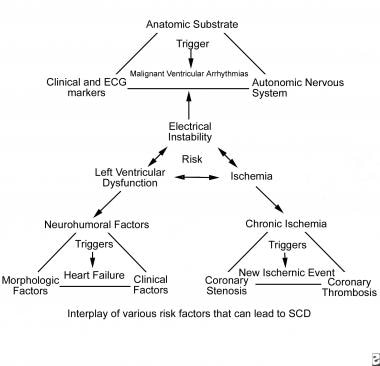

Sudden Cardiac Death

www.rsimmanuel.comSudden cardiac death

Sudden Cardiac Death

www.rsimmanuel.comSudden cardiac death

Sudden Cardiac Death

reference.medscape.comSudden Cardiac Death

reference.medscape.comSudden Cardiac Death